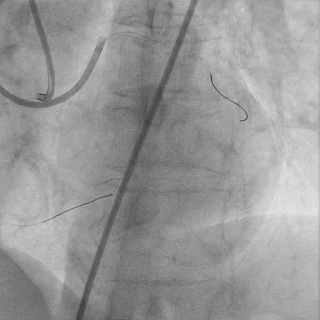

对角支送入IVUS导管,在IVUS实时指引下用尝试穿刺闭塞段

导丝未能进入闭塞段,导丝进入间隔支

逆向造影指引下继续尝试穿刺闭塞段

导丝远端与逆向造影不重叠,未在血管真腔

反复调整导丝最终进入D2#,可见导丝远端与D2侧枝重叠,证明远端位于真腔

微导管交换工作导丝至D2#远端